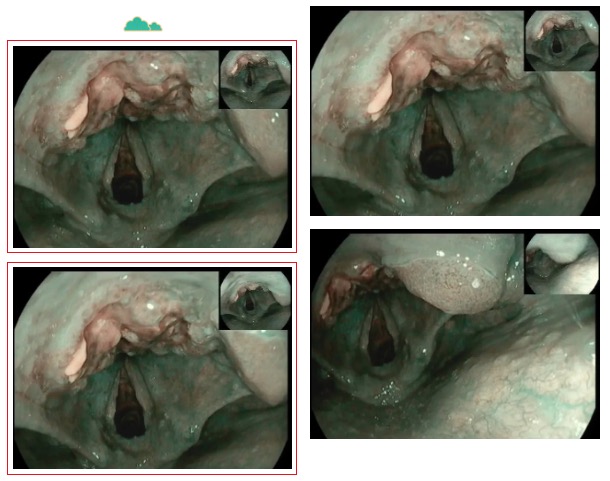

走進(jìn)6診,是一位71歲急診檢查的患者,患者胃內(nèi)大量食物潴留,視野欠清,胃竇及幽門見一不規(guī)則環(huán)形腫物,腫物表面污穢不平,管腔狹窄,內(nèi)鏡無法通過,胃竇前壁見約1.5*1.2cm丘狀隆起,中央凹陷。內(nèi)鏡醫(yī)生陳大夫給予病理活檢,待病理結(jié)果出來行進(jìn)一步治療。

走進(jìn)7診,是一位76歲懷疑胃癌伴幽門不全梗阻的患者,同樣在胃竇、幽門處見環(huán)形不規(guī)則隆起腫物致幽門狹窄,鏡身無法通過。